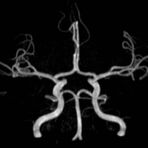

MR-Angiografie (MRA)

Angiographie ohne Kontrastmittel

• MR-Angiografie ohne Kontrastmittel

• Time of Flight (TOF)-Angiographie

• Phasenkontrastangiographie (PCA). Geeignet zur Quantifizierung Stenose-/Insuffizienzgrad z.B. bei Herzklappen, falls echokardiographisch die Untersuchungsbedingungen eingeschränkt sind.

Je nach Fragestellung und Körperregion Gefäßdarstellung ohne Kontrastmittel bei Kontrastmittelunverträglichkeit oder terminaler Niereninsuffizienz möglich.